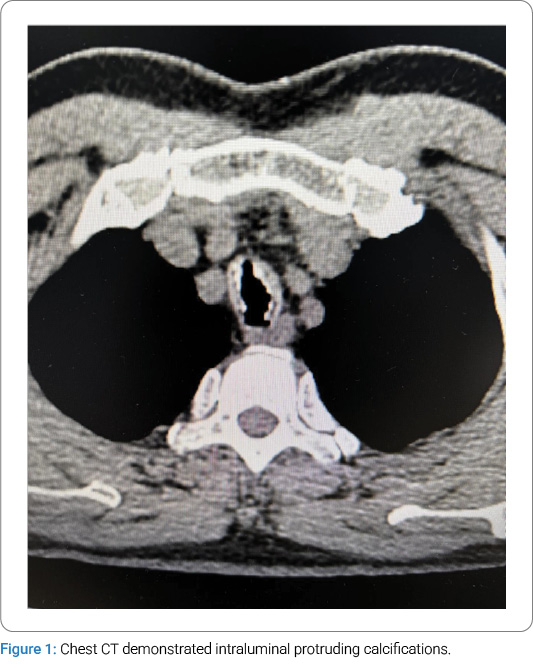

- Multiple calcifications involving the tracheal and main bronchial walls, with partial protrusion into the lumen, are suspicious for Tracheobronchopathia osteochondroplastica (TBPO) or other etiologies.

Diagnostic and Therapeutic Process:Following admission, preoperative preparations were promptly completed. On January 14, 2025, the patient was scheduled for a laparoscopic cholecystectomy under general anesthesia with endotracheal intubation. Routine anesthetic induction was administered with sufentanil 50 μg, midazolam 2 mg, etomidate 12 mg, and rocuronium 50 mg. After an adequate anesthetic effect was achieved, a video laryngoscope was inserted for endotracheal intubation, during which abnormal mucosal proliferation was noted in the trachea below the glottis (Figure 2). A senior anesthesiologist was consulted, and a visual stylet was utilized, revealing extensive proliferation distal to the glottis. A review of the chest CT demonstrated intraluminal protruding calcifications (Figure 1). Mask ventilation was maintained, and neuromuscular blockade was reversed. Following the patient’s full recovery of consciousness, the attending physician informed the patient’s family of the need for further investigations to clarify the airway pathology. The surgery was canceled, and the patient was transferred back to the ward. Subsequent flexible laryngoscopy and bronchoscopy revealed irregular exophytic lesions involving the trachea from the subglottic regionto the carina, accompanied by tracheal stenosis. Multiple scattered nodular changes were observed in the airway, with severe stenosis in the lower tracheal segment precluding bronchoscopic passage. Three biopsy specimens were obtained from the upper and middle tracheal segments and submitted for pathological examination. Pathological diagnosis: Chronic inflammatory cell infiltration of the mucosa, with squamous metaplasia and abundant calcified deposits.